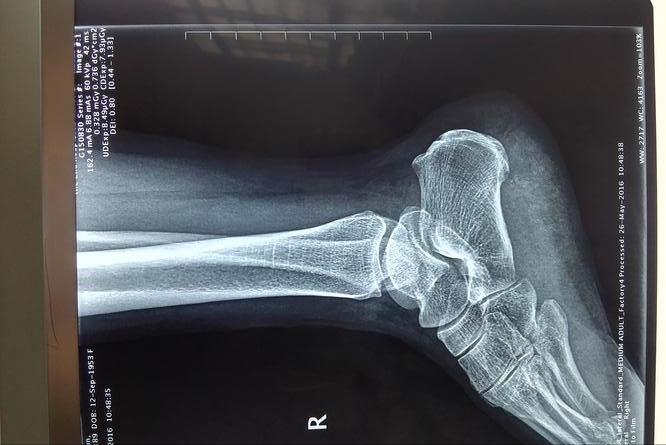

去医院检查,说是足底筋膜炎引发的足跟痛,还有轻微的跟腱炎,开了消炎止痛的药膏和口服药,让少走路、多休息。本以为吃了药就能缓解,可停药没几天,脚后跟又开始疼,而且脚后跟还出现了发麻酸胀的情况,来来回回折腾了好几次,始终没彻底好。